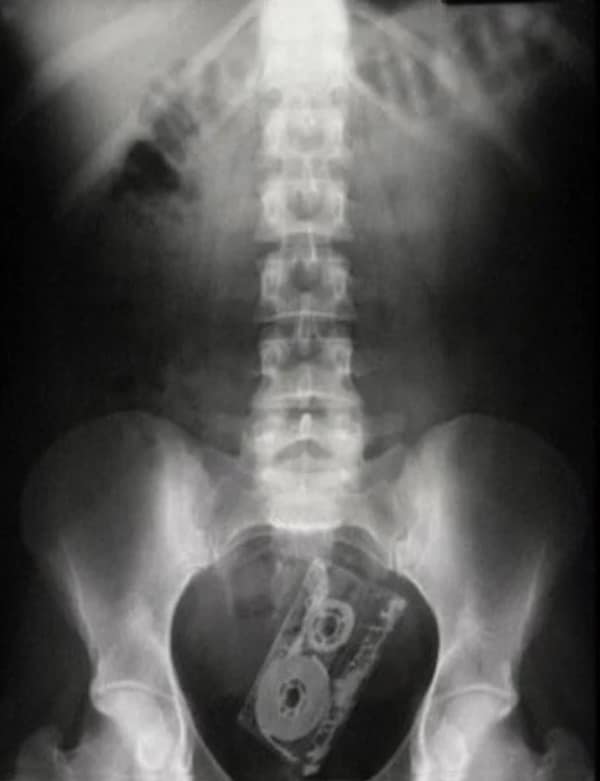

Weird xray photos

I used to think that nothing could surprise me anymore—until I stumbled upon some weird x-ray photos that made me reconsider my stance on human ingenuity (or lack thereof). Apparently, some people have a knack for getting objects lodged where they absolutely shouldn’t be. If you’ve ever wondered how not to use everyday items, these images might provide some unintended guidance.

This collection showcases 31 bizarre x-ray images that defy logic and anatomy textbooks alike. Each photo reveals unexpected objects making cameo appearances inside the human body, turning medical imaging into a gallery of the absurd. From common household items inexplicably found in unusual places to anomalies that would leave even seasoned doctors scratching their heads, these images offer a perplexing glimpse into the more “creative” side of medical emergencies. They highlight the intersection of curiosity, misadventure, and perhaps a dash of poor decision-making, all captured through the lens of radiology.